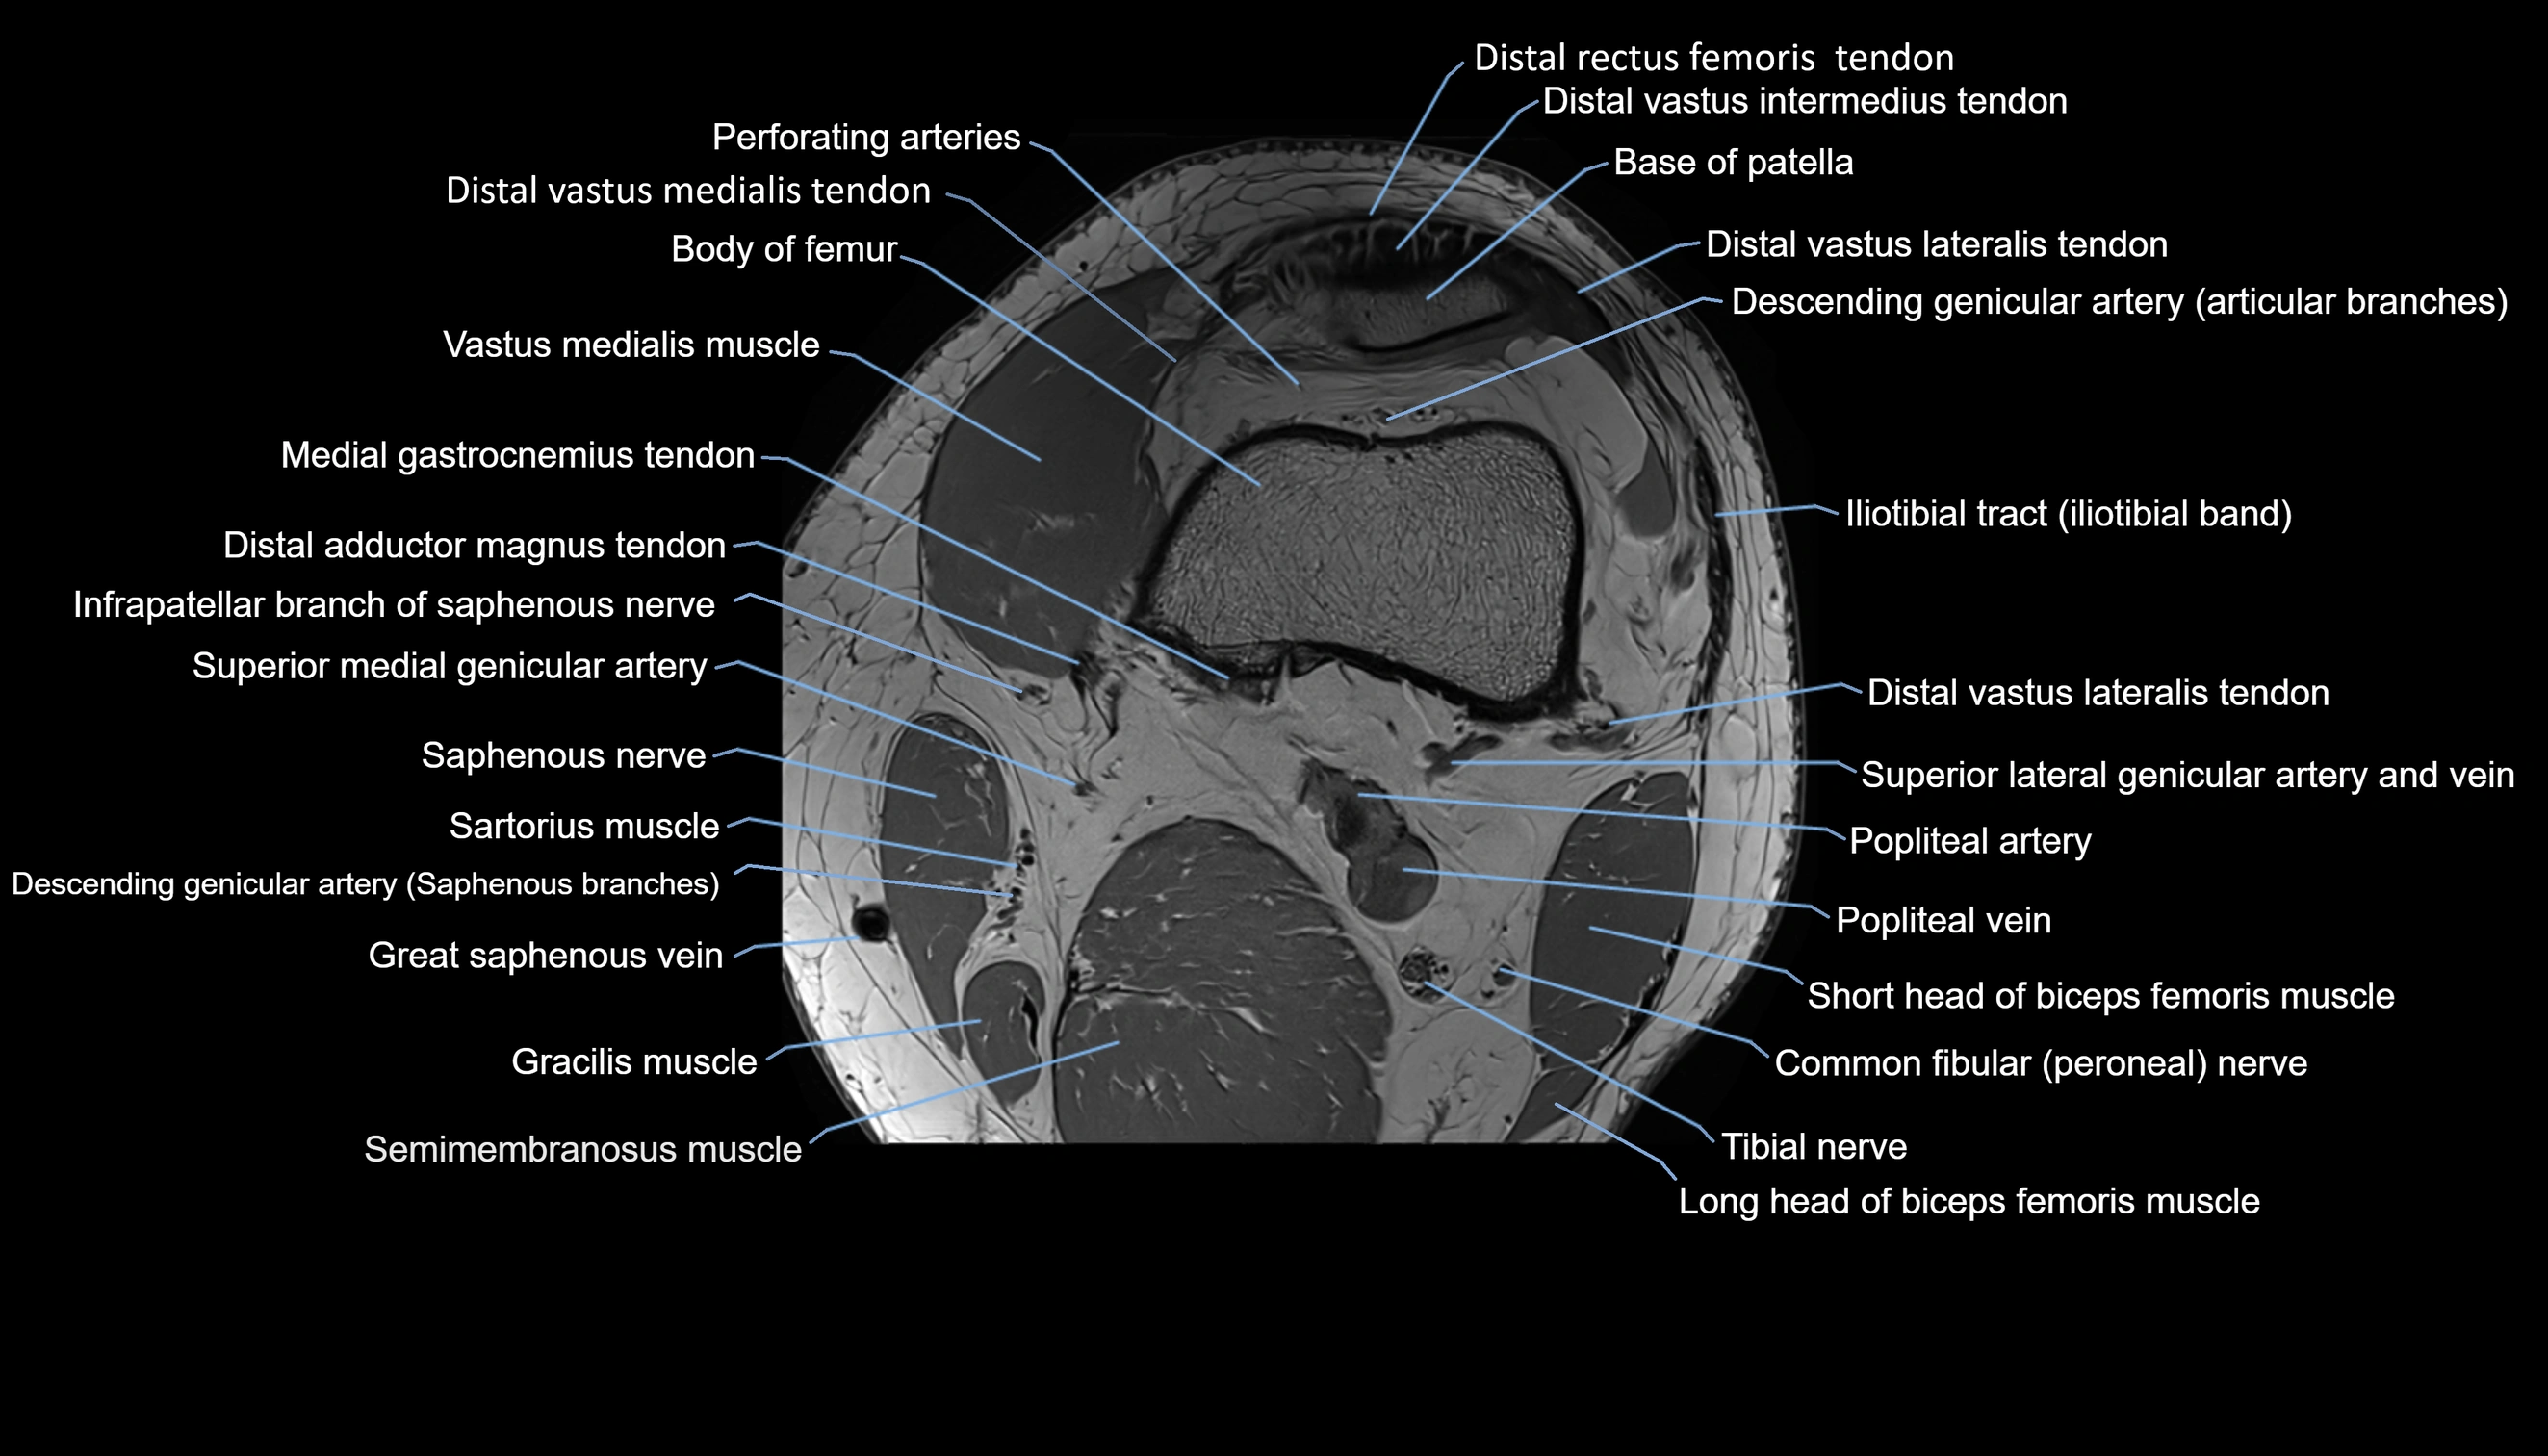

- Perforating Arteries (Knee joint)

- Popliteal artery

- Popliteal vein

- Saphenous nerve

- Sartorius muscle

- Semimembranosus muscle

- Tibial nerve

- great saphenous vein